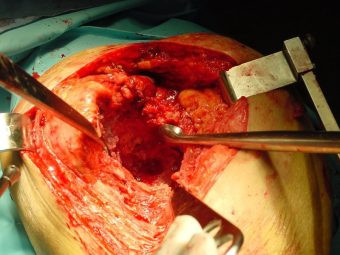

Prótesis Total de Cadera por Fractura

Envíado por Dr. Ricardo Antonio Gómez G.